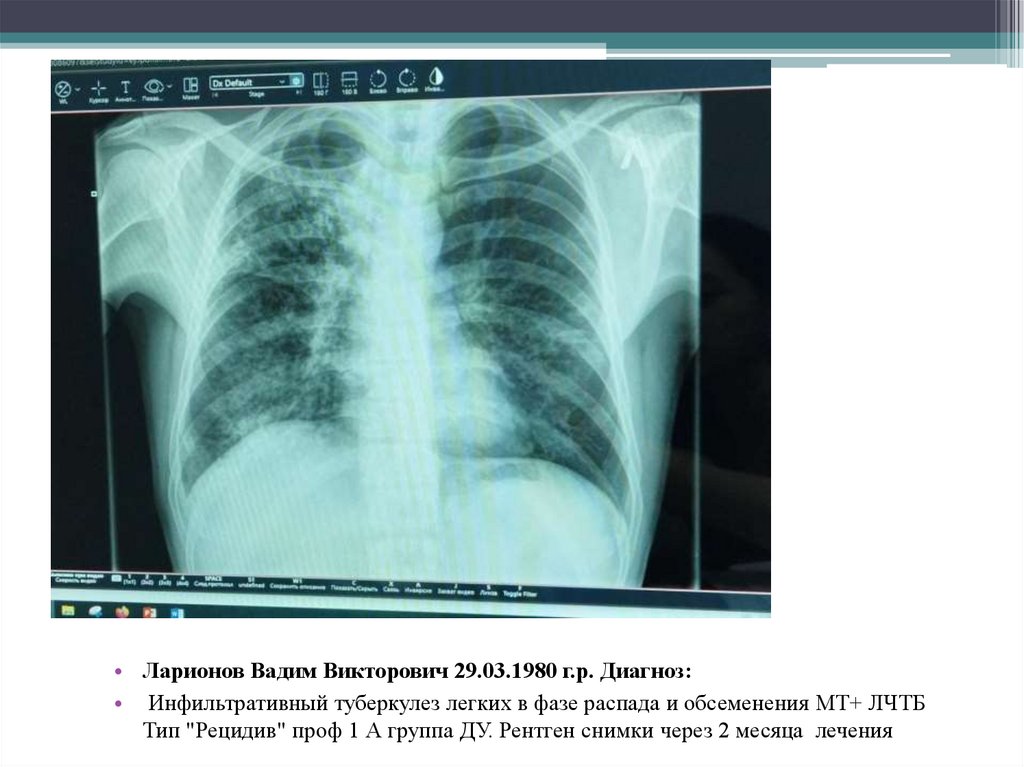

• Ларионов Вадим Викторович

29.03.1980 г.р.

Диагноз:

Инфильтративный туберкулез легких в фазе

распада и обсеменения МТ+ ЛЧТБ Тип

"Рецидив" проф 1 А группа ДУ.

• Ларионов Вадим Викторович 29.03.1980 г.р. Диагноз:

• Инфильтративный туберкулез легких в фазе распада и обсеменения МТ+ ЛЧТБ

Тип "Рецидив" проф 1 А группа ДУ. Рентген снимки через 2 месяца лечения